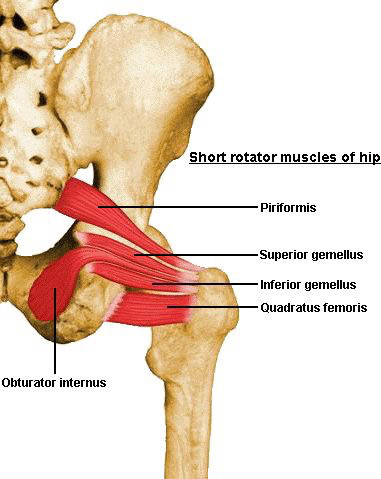

【症例】股関節/骨盤の痛み、鼠径部(股の付け根)の痛み

【症例】股関節/骨盤の痛み、鼠径部(股の付け根)の痛み

梨状筋 "Figure 4 Stretch" (初級編)

梨状筋 "Figure 4 Stretch" (初級編)

Foam Roller Exercise - Piriformis(梨状筋)

Foam Roller Exercise - Piriformis(梨状筋)

お尻の筋膜リリース

お尻の筋膜リリース